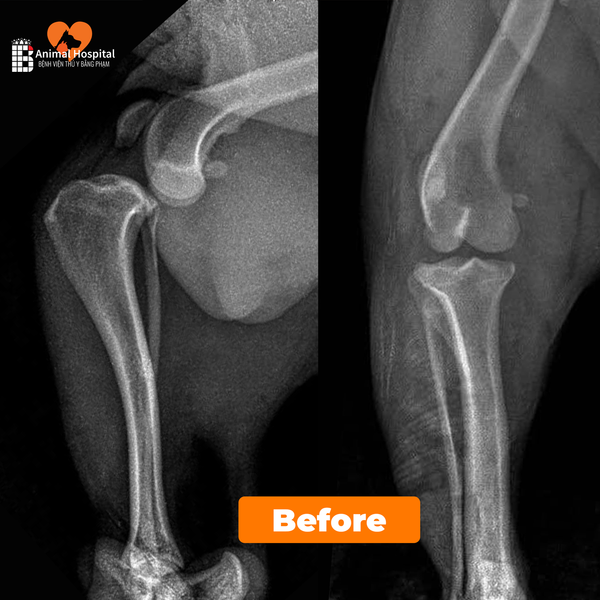

• X-quang khớp gối: thấy trượt mâm chày ra trướctrật xương bánh chè trong độ II.

• Không phát hiện tổn thương xương khác.

đứt dây chằng chéo trước ở chó

Chẩn đoán xác định:

→ Đứt dây chằng chéo trước kèm trật xương bánh chè trong.